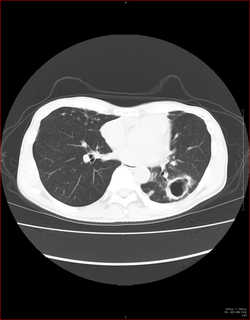

CTで見ると…

3Dだと、こうなります。

気管狭窄ですね。こういう所見もレントゲンで捉えることができるのです。